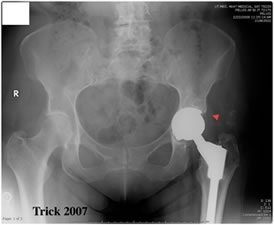

MoM bearing surfaces have encountered varied results over the years. The ability of offering larger diameter heads has increased the usage of MoM as one of the mechanisms to reduce hip dislocations. However, issues have been raised with regards to cup spinout, high trace elements, and metal sensitivity.

L. Keppler - cup spin out 7 weeks post-op |

MoM cup migration 2 years post-op |